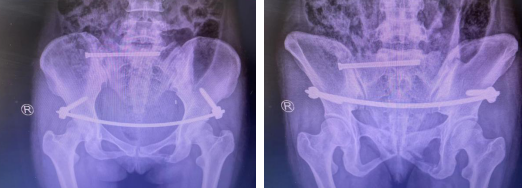

术后即刻

经充分术前准备并与患者沟通,任海东、信远、吴学业医疗团队对患者实施了微创手术,用时30分钟便成功完成了手术,仅2个3cm左右的手术切口,出血量非常小。术后第二天,患者能够在床上坐起,功能恢复良好。患者术后4-7天即可安排出院。

经皮骨盆前环infix内支架固定技术是治疗骨盆前环损伤的一种新型微创内固定方法,取双侧髂前下棘皮肤小切口植入椎弓根螺钉,两螺钉间建立皮下隧道,连接杆经过皮下隧道连接椎弓根螺钉后,通过间接复位技术使骨盆骨折复位并固定。该技术具有手术时间短、创伤小,保护骨块的血供,减少局部软组织疤痕等特点,结合了内固定和外固定的优点,有效避免了术后深部感染及使用外固定的手术并发症。术后患者恢复快、对日常生活影响小,能够有效减轻患者的精神和经济负担。

“经皮骨盆前环infix内支架固定技术适用于骨盆前环骨折及脱位的患者,它最大的特点是微创,相对传统切开复位手术来说,这就是一个“小手术”,能够减轻和消除患者的手术恐惧心理。另外,费用低,易于被患者接受。从术后CT上看,患者的骨盆环稳定性恢复良好,患者都很满意。”任海东主任说道。